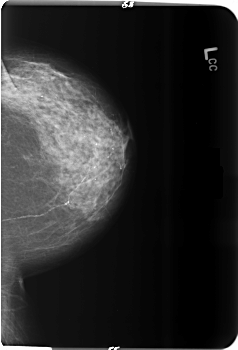

B_3513_1.LEFT_CC

LEFT_CC LINES 5936 PIXELS_PER_LINE 4040 BITS_PER_PIXEL 12 RESOLUTION 50 NON_OVERLAY